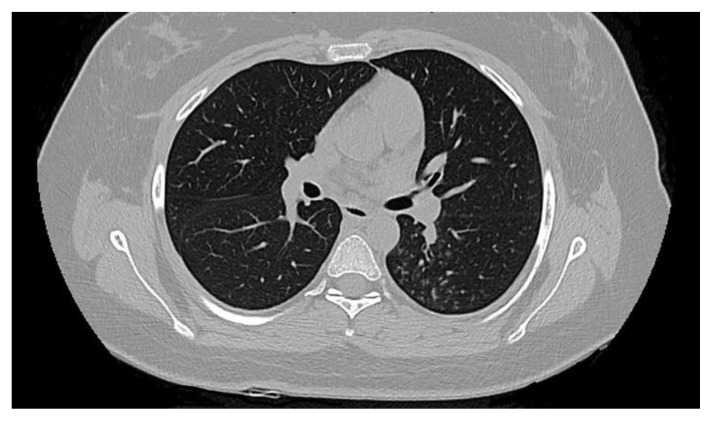

Results: We accrued 62 patients, of whom 7 (11,3%) tested positive, without any symptoms or signs of active TB, and 2 (3,2%) resulted as indeterminate. All positive patients started prophylaxis with isoniazid 300 mg daily, while patients whose test was indeterminate did not receive any prophylaxis. Active TB was excluded by imaging, as well as microscopic, cultural, and molecular examination on bronchoalveolar lavage if signs of any infection were detected. During the 46 months of observation, no patients developed TB reactivation.

Abstract Image